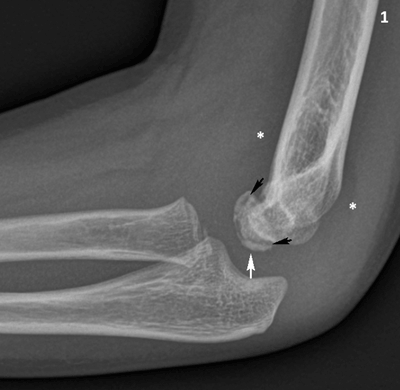

Figure 1

Conventional radiography of the right elbow, lateral view. The capitellum has a slightly irregular articular contour (white arrow) and there is a radiolucent line in the subchondral bone (black arrows). Note slight joint effusion with displacement of the elbow fad pads (asterisks).